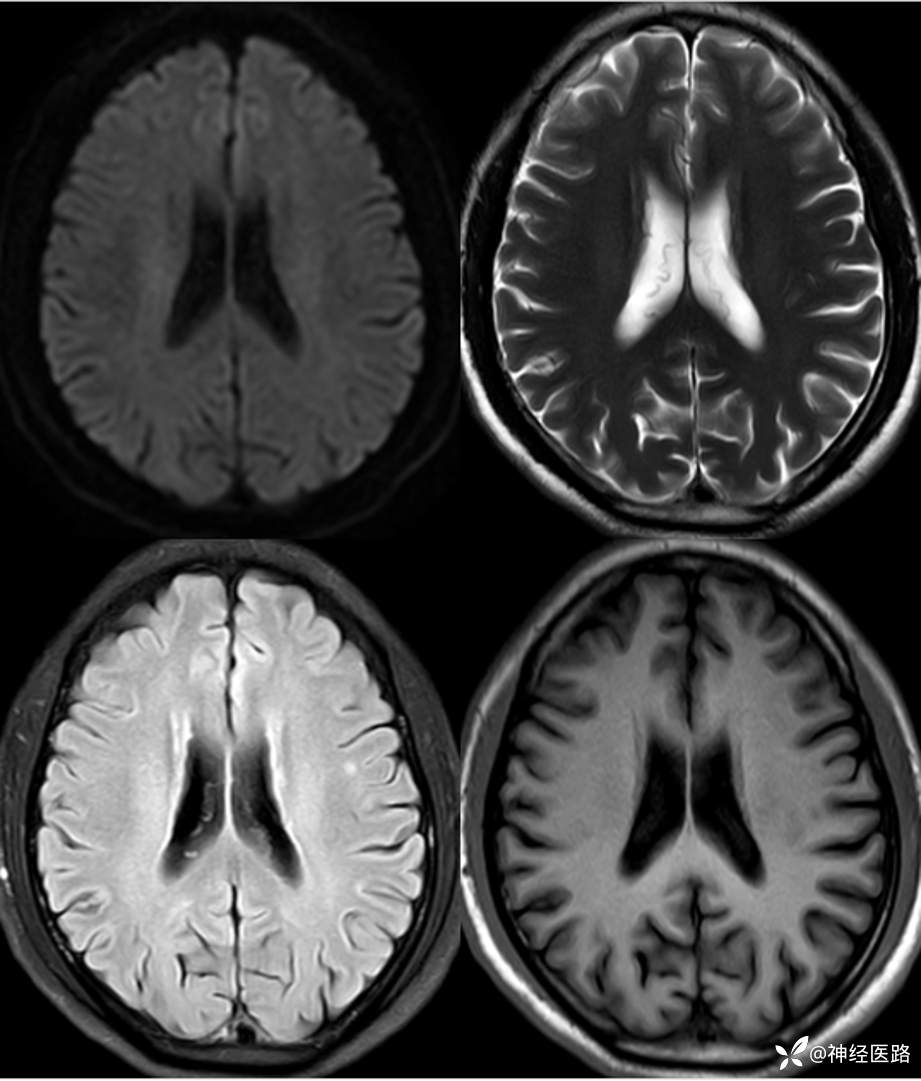

辅助检查:头部磁共振:1.颅脑DWI未见明显异常扩散受限。 2.脑白质高信号,脑萎缩。3.双侧上颌窦、双侧筛窦、双侧额窦炎。

补充1年余前直立倾斜试验、肌电图及头部磁共振检查资料。

两次影像对比